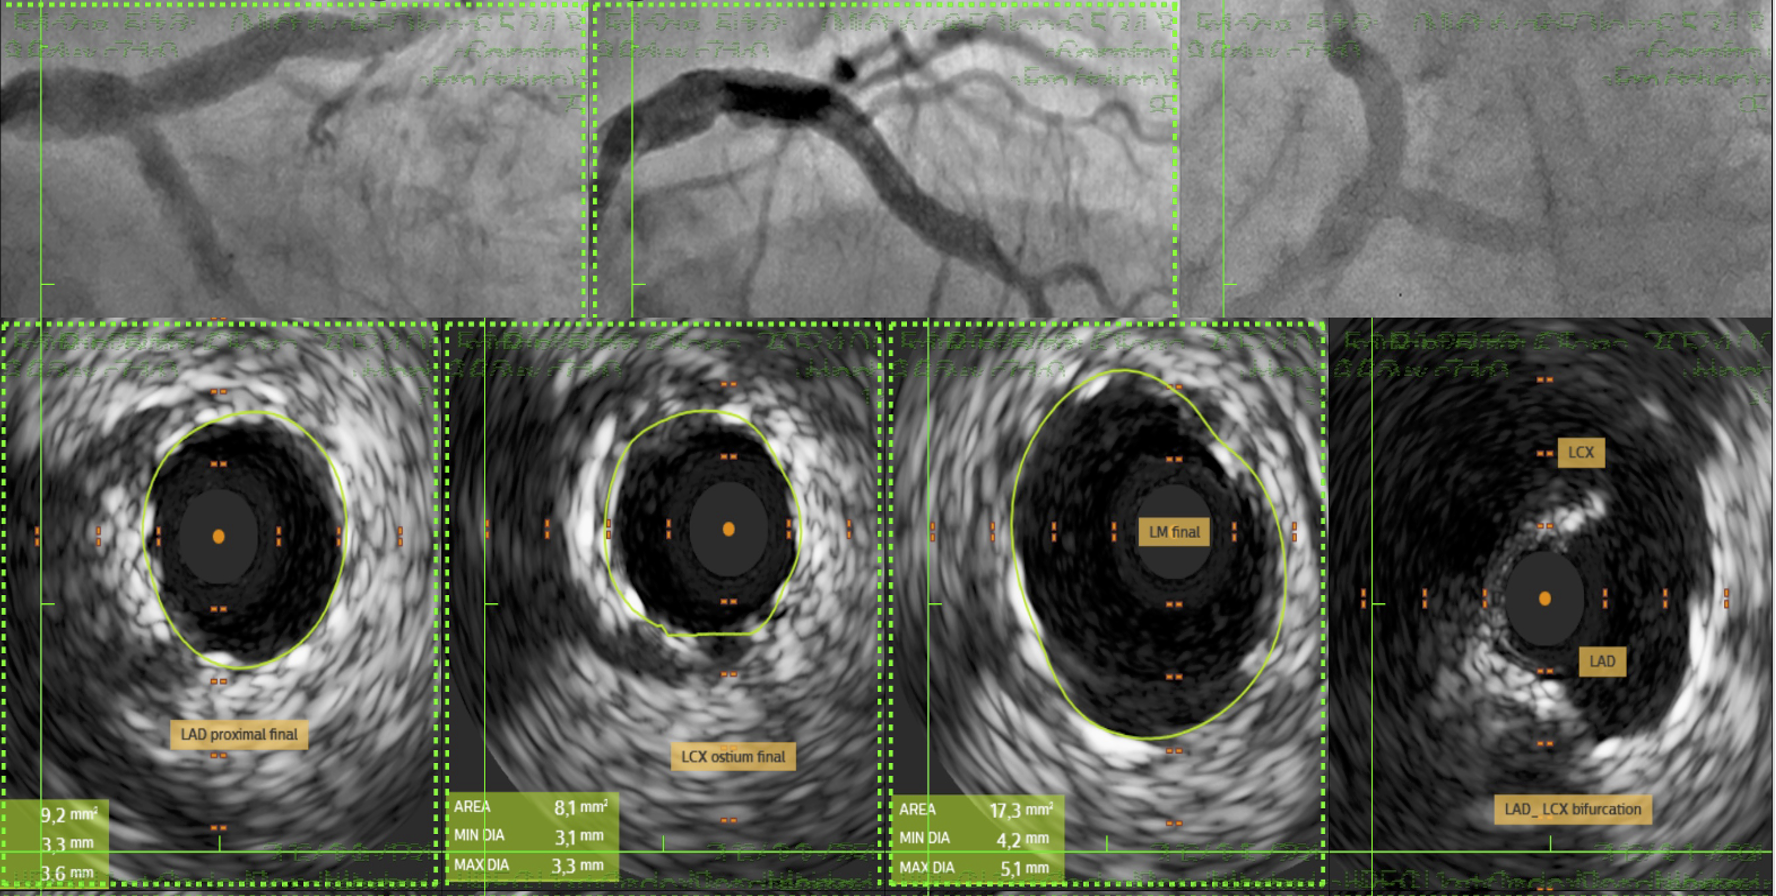

The procedure commenced with IABP insertion and the use of a 7F XB guiding catheter for an antegrade approach. A wire was advanced across the LM-LAD stenosis, and predilatation with a 2.5 mm semicompliant (SC) balloon revealed the faint ostium of the occluded LCx. A 45¡Æ angulated microcatheter facilitated the crossing of the LCx occlusion with a stiff wire, which was then exchanged for a standard workhorse wire.Following LCx predilatation, kissing balloon pre-dilation of the LM-LAD-LCx bifurcation was performed. A 3.0x18 mm Sirolimus stent was deployed in the proximal LAD. Subsequently, a 2.75x18 mm Sirolimus stent was placed in the LCx with minimal protrusion into the LM and crushed with a 3.5 mm non-compliant (NC) balloon. The crushed stent struts were recrossed, predilated with sequential SC balloons, and a distal optimization (DOT) was performed. A second kissing balloon inflation followed.A third Sirolimus stent (4.0x25 mm) was then overlapped with the previous stent in the LAD-LM segment. After a proximal optimization technique (POT) in the LM, the LCx was rewired. Final optimization included further DOT in both the LAD and LCx, a final triple kissing balloon inflation, and a concluding POT. An excellent final result was confirmed by IVUS (LAD area 9.2 mm©÷; LCx area 8.1 mm©÷; minimal lumen area 16 mm©÷) and angiography, after which the IABP was removed.

A 65-year-old woman with complex coronary disease, including distal left main stenosis and a chronic occluded LCx ostium, successfully underwent percutaneous intervention using a DK-crush stenting technique after refusing surgery. The challenging LCx origin, identified after LM-LAD predilatation, was crossed using a 45¡Æ angulated microcatheter. The patient remained asymptomatic with excellent therapy compliance at follow-up. The procedure's success was confirmed by IVUS, demonstrating the efficacy of tailored percutaneous approaches for complex lesions.